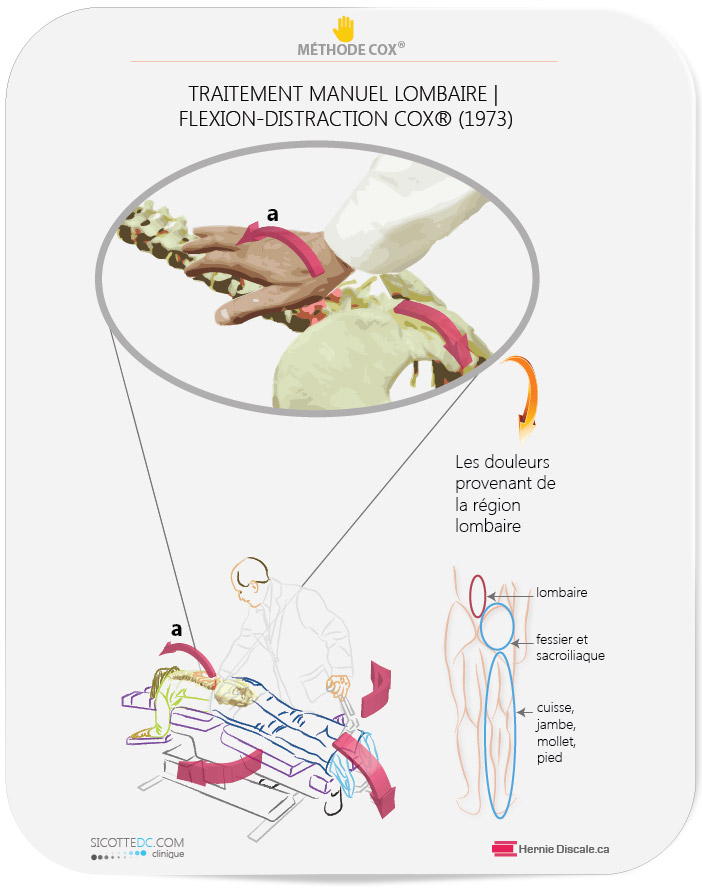

- diminue la mobilité lombaire altère la biomécanique de la région lombaire,

- pince les nerfs lombaires,

- crée de l’adhésion capsulaire,

COMMENT LE TRAITEMENT NATUREL COX® AIDE À DIMINUER LES EFFETS NÉFASTES DE L’ARTHROSE LOMBAIRE

L’objectif est de mobiliser les segments où se trouve la discarthrose (discopathie) vertébrale.

COMMENT FONCTIONNE UN TRAITEMENT COX®